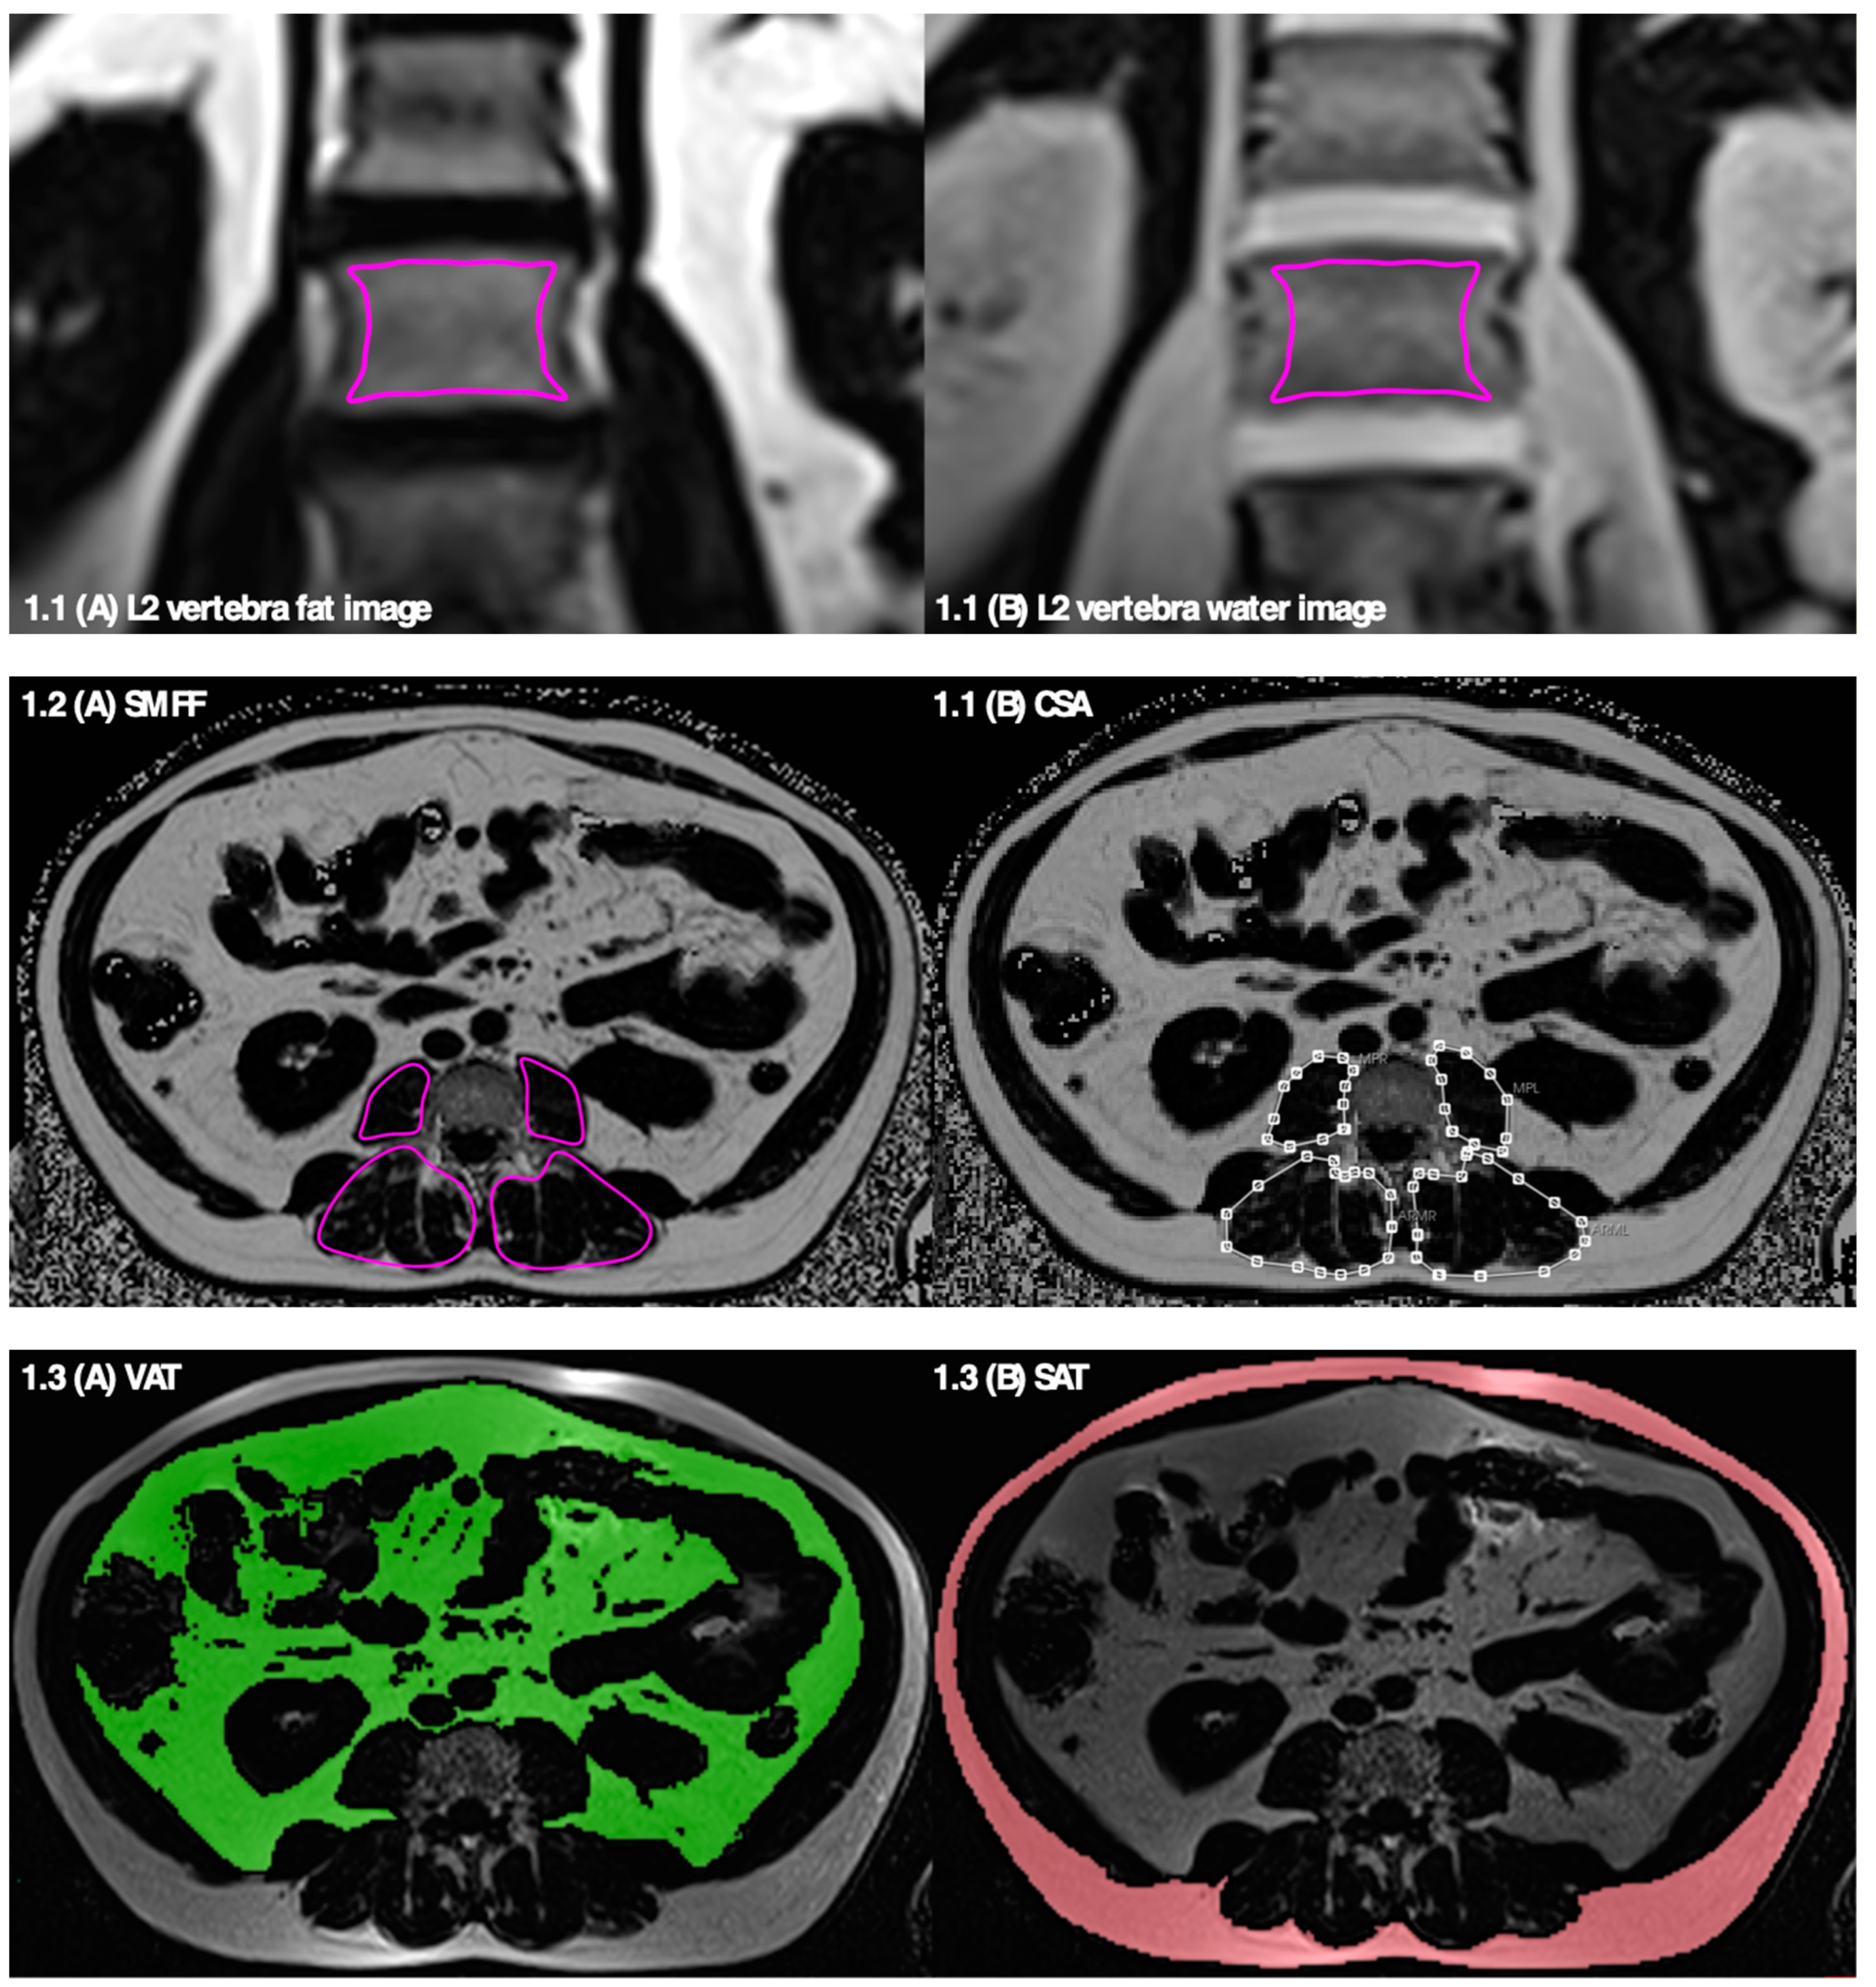

2.2.1. Bone Marrow Fat Fraction—Osteopenia

2.2.2. Skeletal Muscle Fat Fraction and Muscle Mass—Sarcopenia

2.2.3. Total, Visceral, and Subcutaneous Adipose Tissue—Adiposity